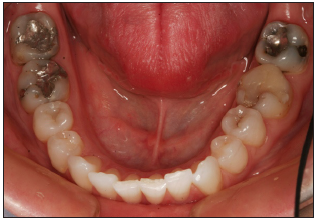

Mandibular arch view

Retractors are required to capture image of the mandibular arch. A high quality mirror should be used to capture reflected image.

The facial surfaces of the central incisors should be visible near the edge of the image. Lips and mirror edges views should not be visible. The nose and maxillary teeth should not appear in image.

To eliminate fog on the mirror, warm the mirror in hot water ahead of time and ask the patient to breathe through their nose. Hitting the mirror with a light stream of air while taking the photo may be helpful as well.

Capture the image at approximately 45 degree angle to the mirror surface. The placement of mirror should allow for the facial and lingual surfaces to be seen at the same time.

Show as many teeth as possible. The central incisors to the mesial of the second molars should be visible. The anterior teeth must be clearly shown. Mandibular teeth and facial and lingual embrasures should be visible.

Image may be captured from in front of the patient. The patient's tongue should be positioned in the posterior position and may be retracted with the occlusal mirror.

Focus on the reflected image of the premolars.

Adjust the focal length as needed to frame the mandibular arch.